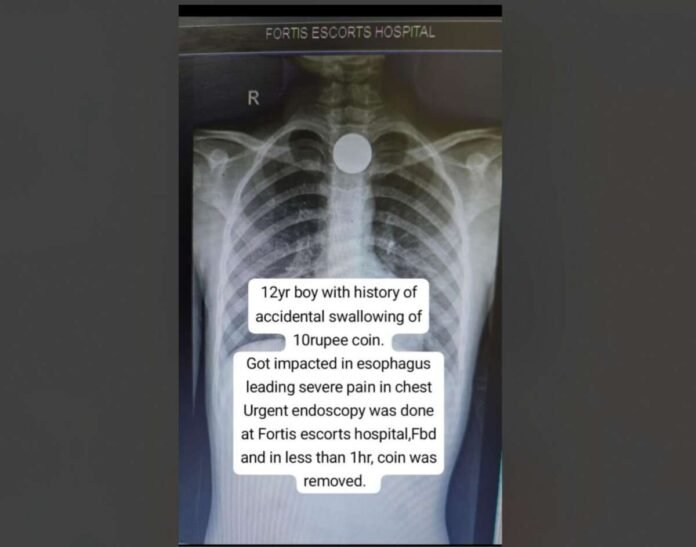

Faridabad, 03 October 2025: A 12‑year‑old child was rushed to the emergency department at Fortis Escorts Faridabad after accidentally swallowing a ₹ 10 coin. The coin, measuring nearly 27 mms in diameter, was lodged in the upper esophagus and was causing intense chest pain and difficulty swallowing. An X‑ray confirmed its presence in the food pipe. Led by Dr. Nirdesh Chauhan, Consultant – Gastroenterologist, Fortis Escorts Faridabad, the medical team opted for an urgent endoscopy to prevent life-threatening complications that could arise from delays, such as esophageal tears, infection, or breathing difficulties. Using specialized endoscopic tools, the medical team successfully removed the coin within an hour of the child’s arrival. The extraction itself took about 15 minutes, after which the child was discharged safely later that evening. Follow‑up inspection confirmed there was no damage caused to the esophagus.